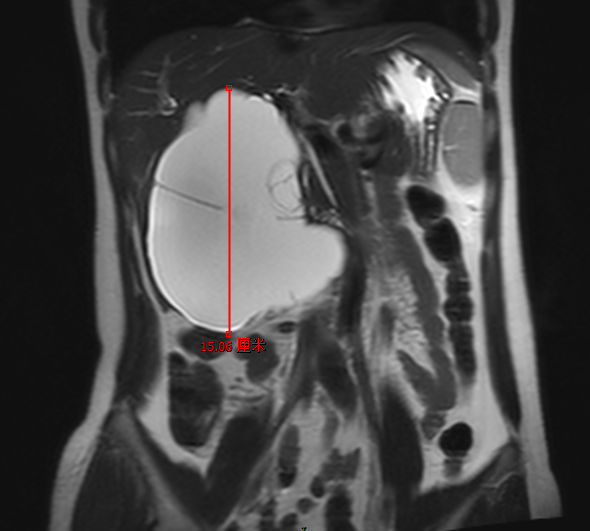

很多朋友體檢發(fā)現(xiàn)了幾毫米或是十幾毫米的肝囊腫,寢食難安,到處尋醫(yī)問(wèn)藥??纯聪旅娌∮训木薮蟾文夷[,是不是小巫見(jiàn)大巫,瞬間輕松。肝囊腫是肝臟常見(jiàn)的良性疾病,連良性腫瘤都算不上,不會(huì)癌變,一般直徑不超過(guò)100毫米對(duì)身體幾乎無(wú)任何影響。往往超過(guò)100毫米且有明顯癥狀的病友可行肝囊腫開(kāi)窗引流術(shù)。手術(shù)也較為簡(jiǎn)單,腹腔鏡微創(chuàng)即可完成,“開(kāi)窗”即在囊腫上切除一塊囊腫壁而已,一般無(wú)需全部切除囊腫,屬于低風(fēng)險(xiǎn)手術(shù)。